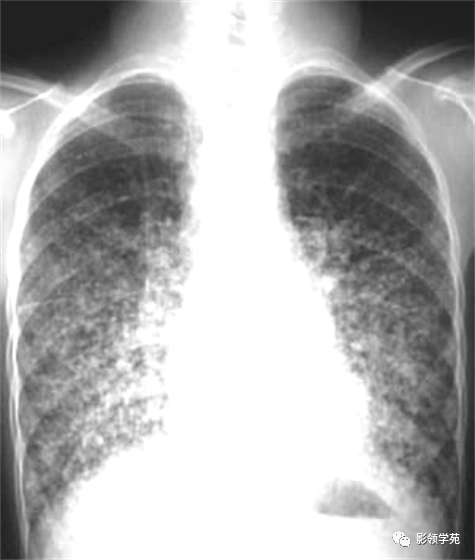

双肺淋巴道转移癌。胸部正位片示双侧中下肺野多发结节状及网格状高密度结节影,可见克氏B线 (下图)